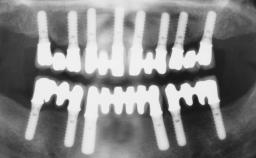

Immediate Loading of Six Implants in the Maxilla and Final Restoration with a Full-Arch Gold/Ceramic FDP Involving the Concept of Tilted Implants

# of Implants 6

Defining Characteristics Fully edentulous upper jaw to be rehabilitated with four or more implants

Modality Fixed hybrid bridge on 5+ implants